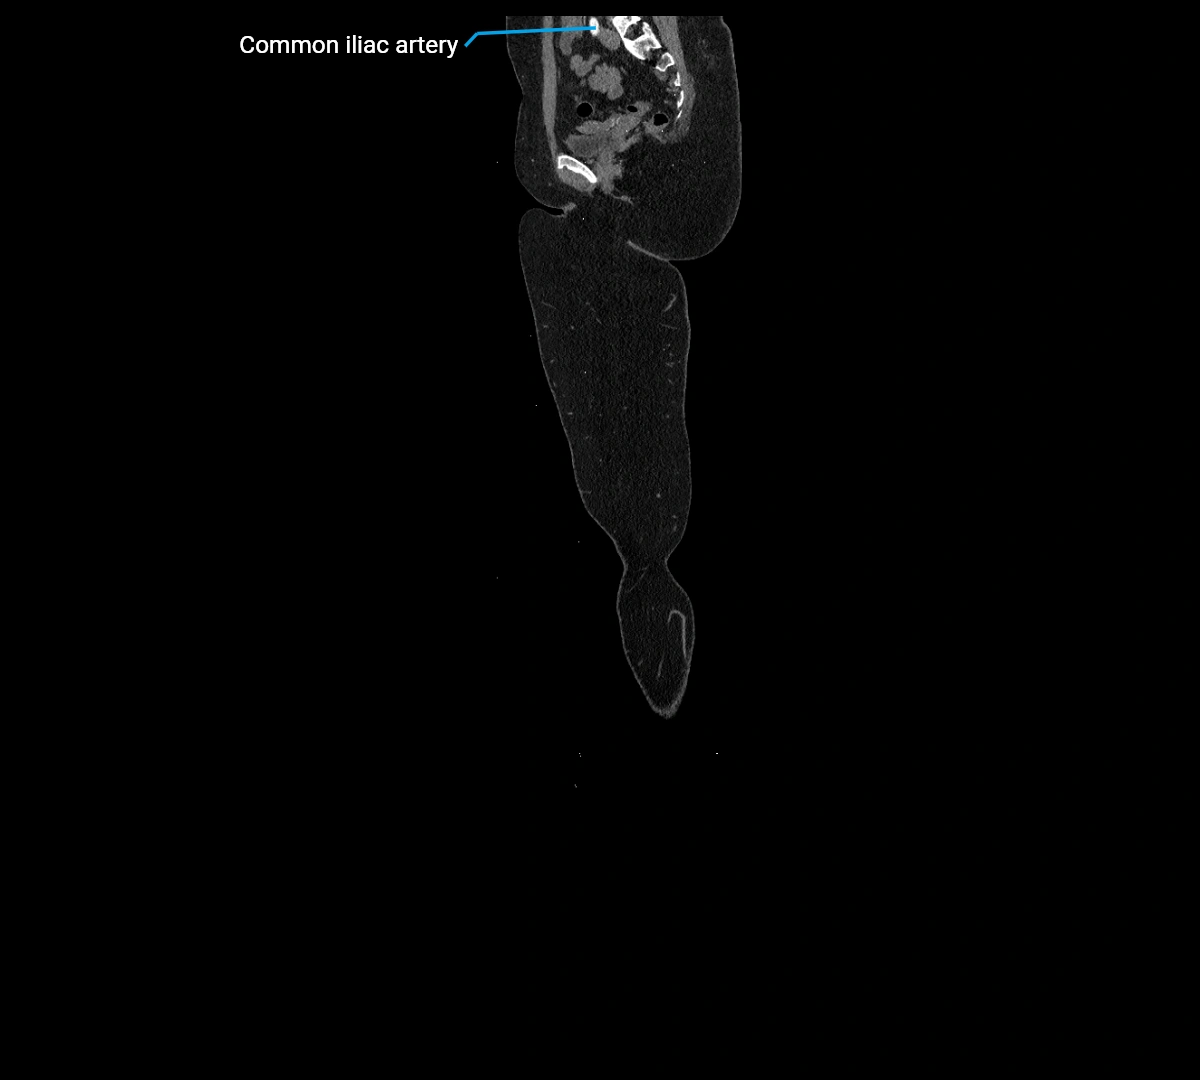

Contrast-enhanced CT (CTA):

• Gold standard for abdominal aortic imaging

• Provides excellent detail of lumen, wall, aneurysm, thrombus, and branch vessels

• Multiplanar and 3D reconstructions help in aneurysm measurement, stent graft planning, and dissection evaluation

• Detects acute rupture, traumatic injury, or occlusion with high sensitivity